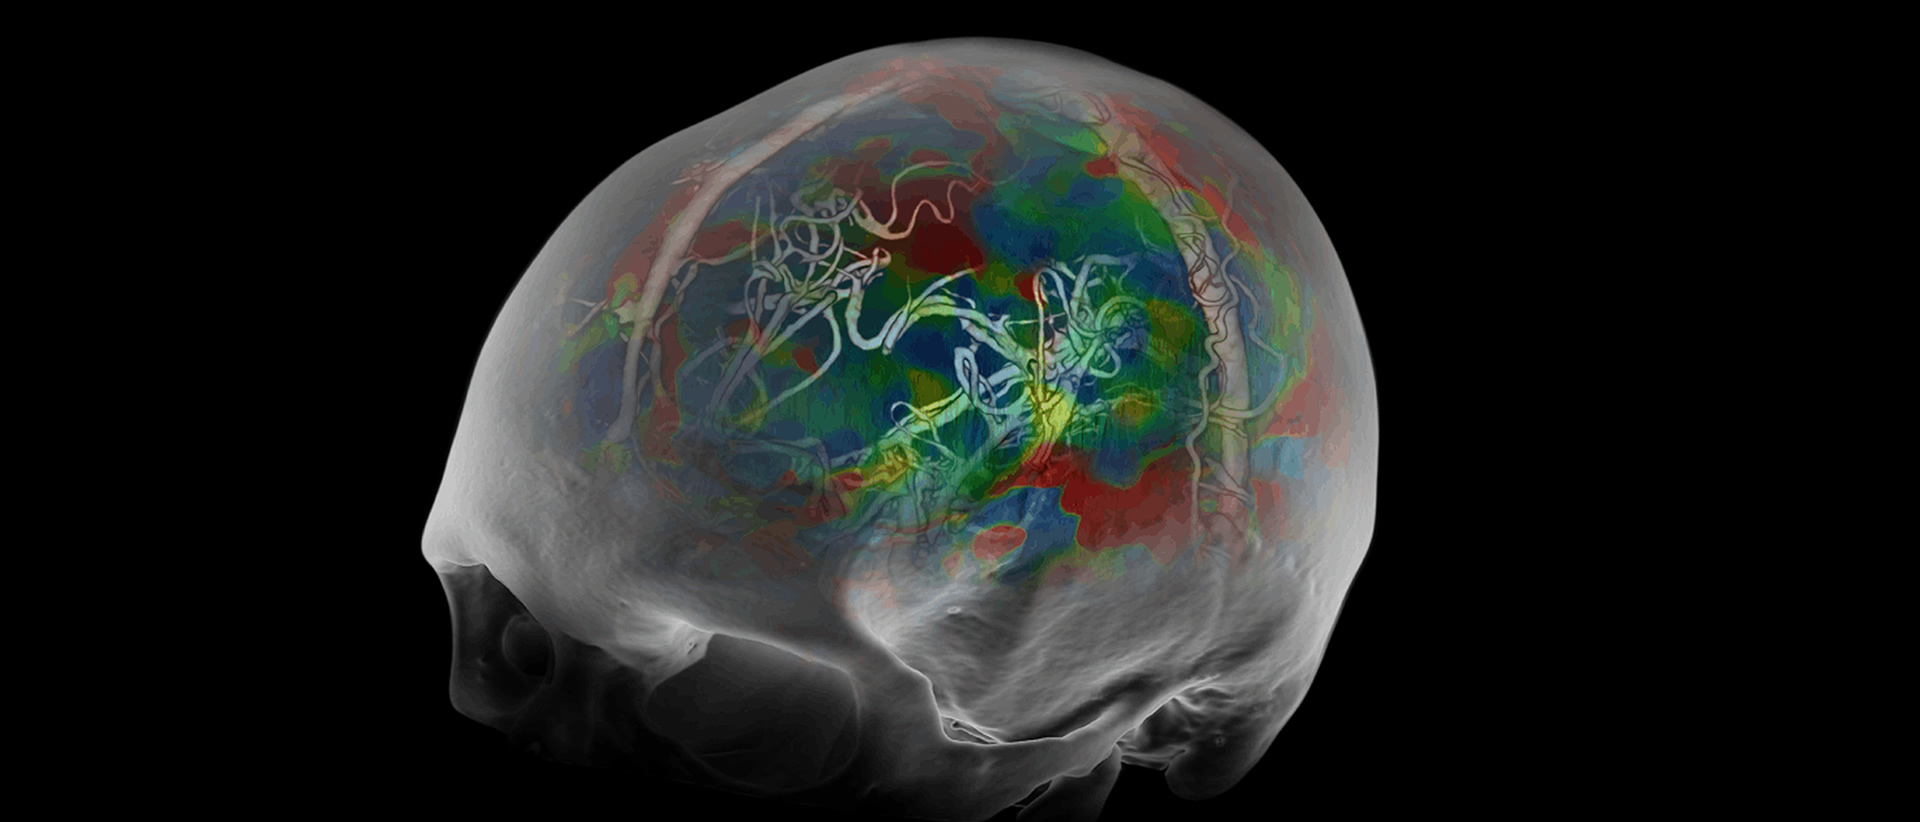

Artículos orientados a Médicos Radiólogos con casos reales de nuestras clínicas